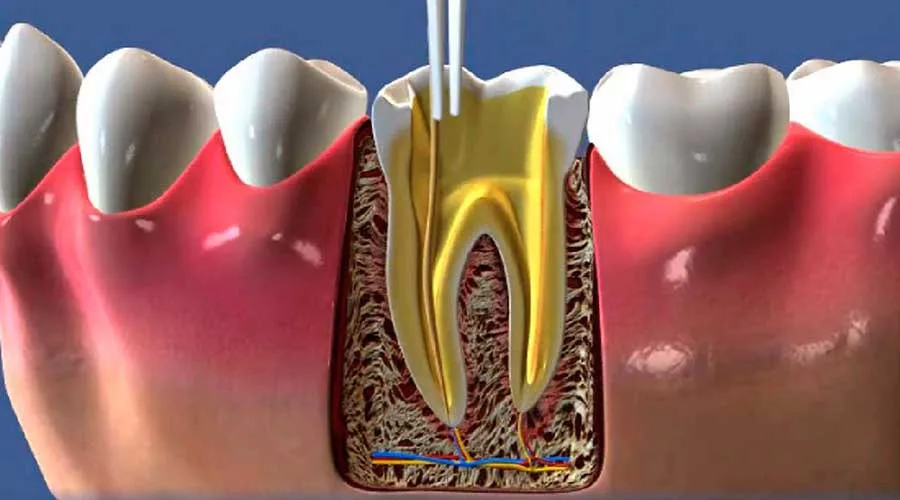

O tratamento de canal remove a polpa inflamada ou infectada.

Etapas do Procedimento

O tratamento geralmente começa com uma avaliação clínica e radiográfica.

Em seguida, o dentista realiza a anestesia local e a remoção da polpa danificada.

Após a limpeza, os canais são desinfetados e selados.